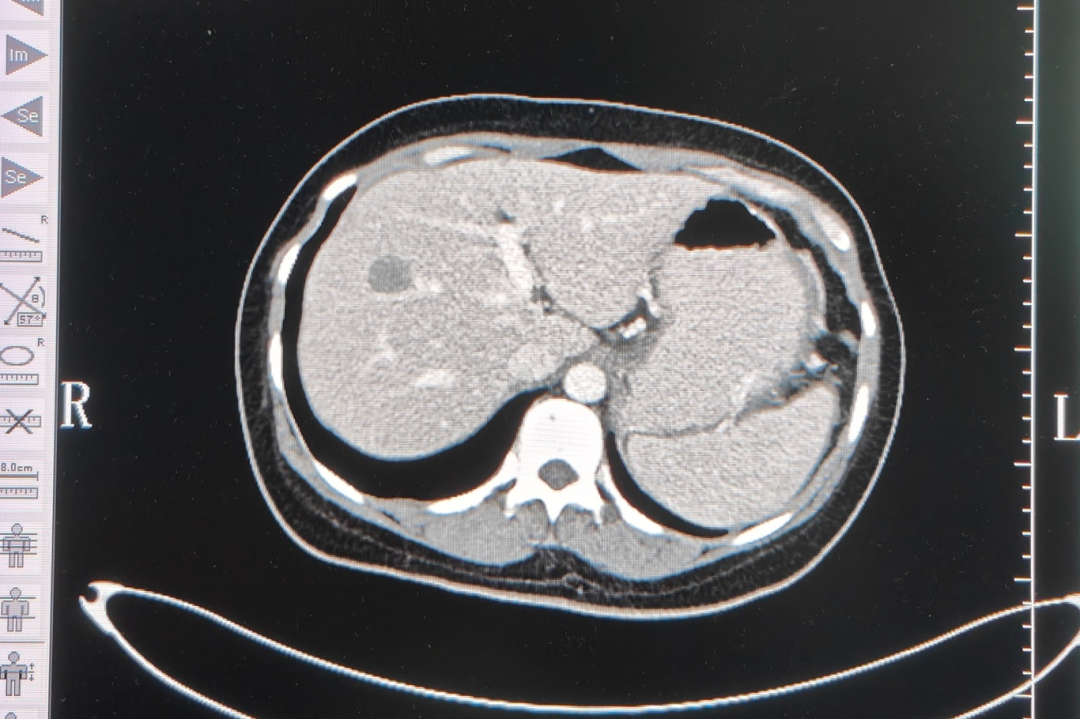

第1次治疗后,小向开始能吃下东西,腹部肿胀也得到了缓解,整个人轻松了不少。令小向夫妇欣喜的是,第3次介入治疗后,影像结果显示,肿瘤普遍缩小至一半以上,有些甚至消失,如肝脏转移瘤较前缩小至4.6cm;胃底贲门区-腹膜后-胰腺体尾部肿瘤较前缩小至7.6cm等等。

▲2022年8月,第三个疗程影像检查结果